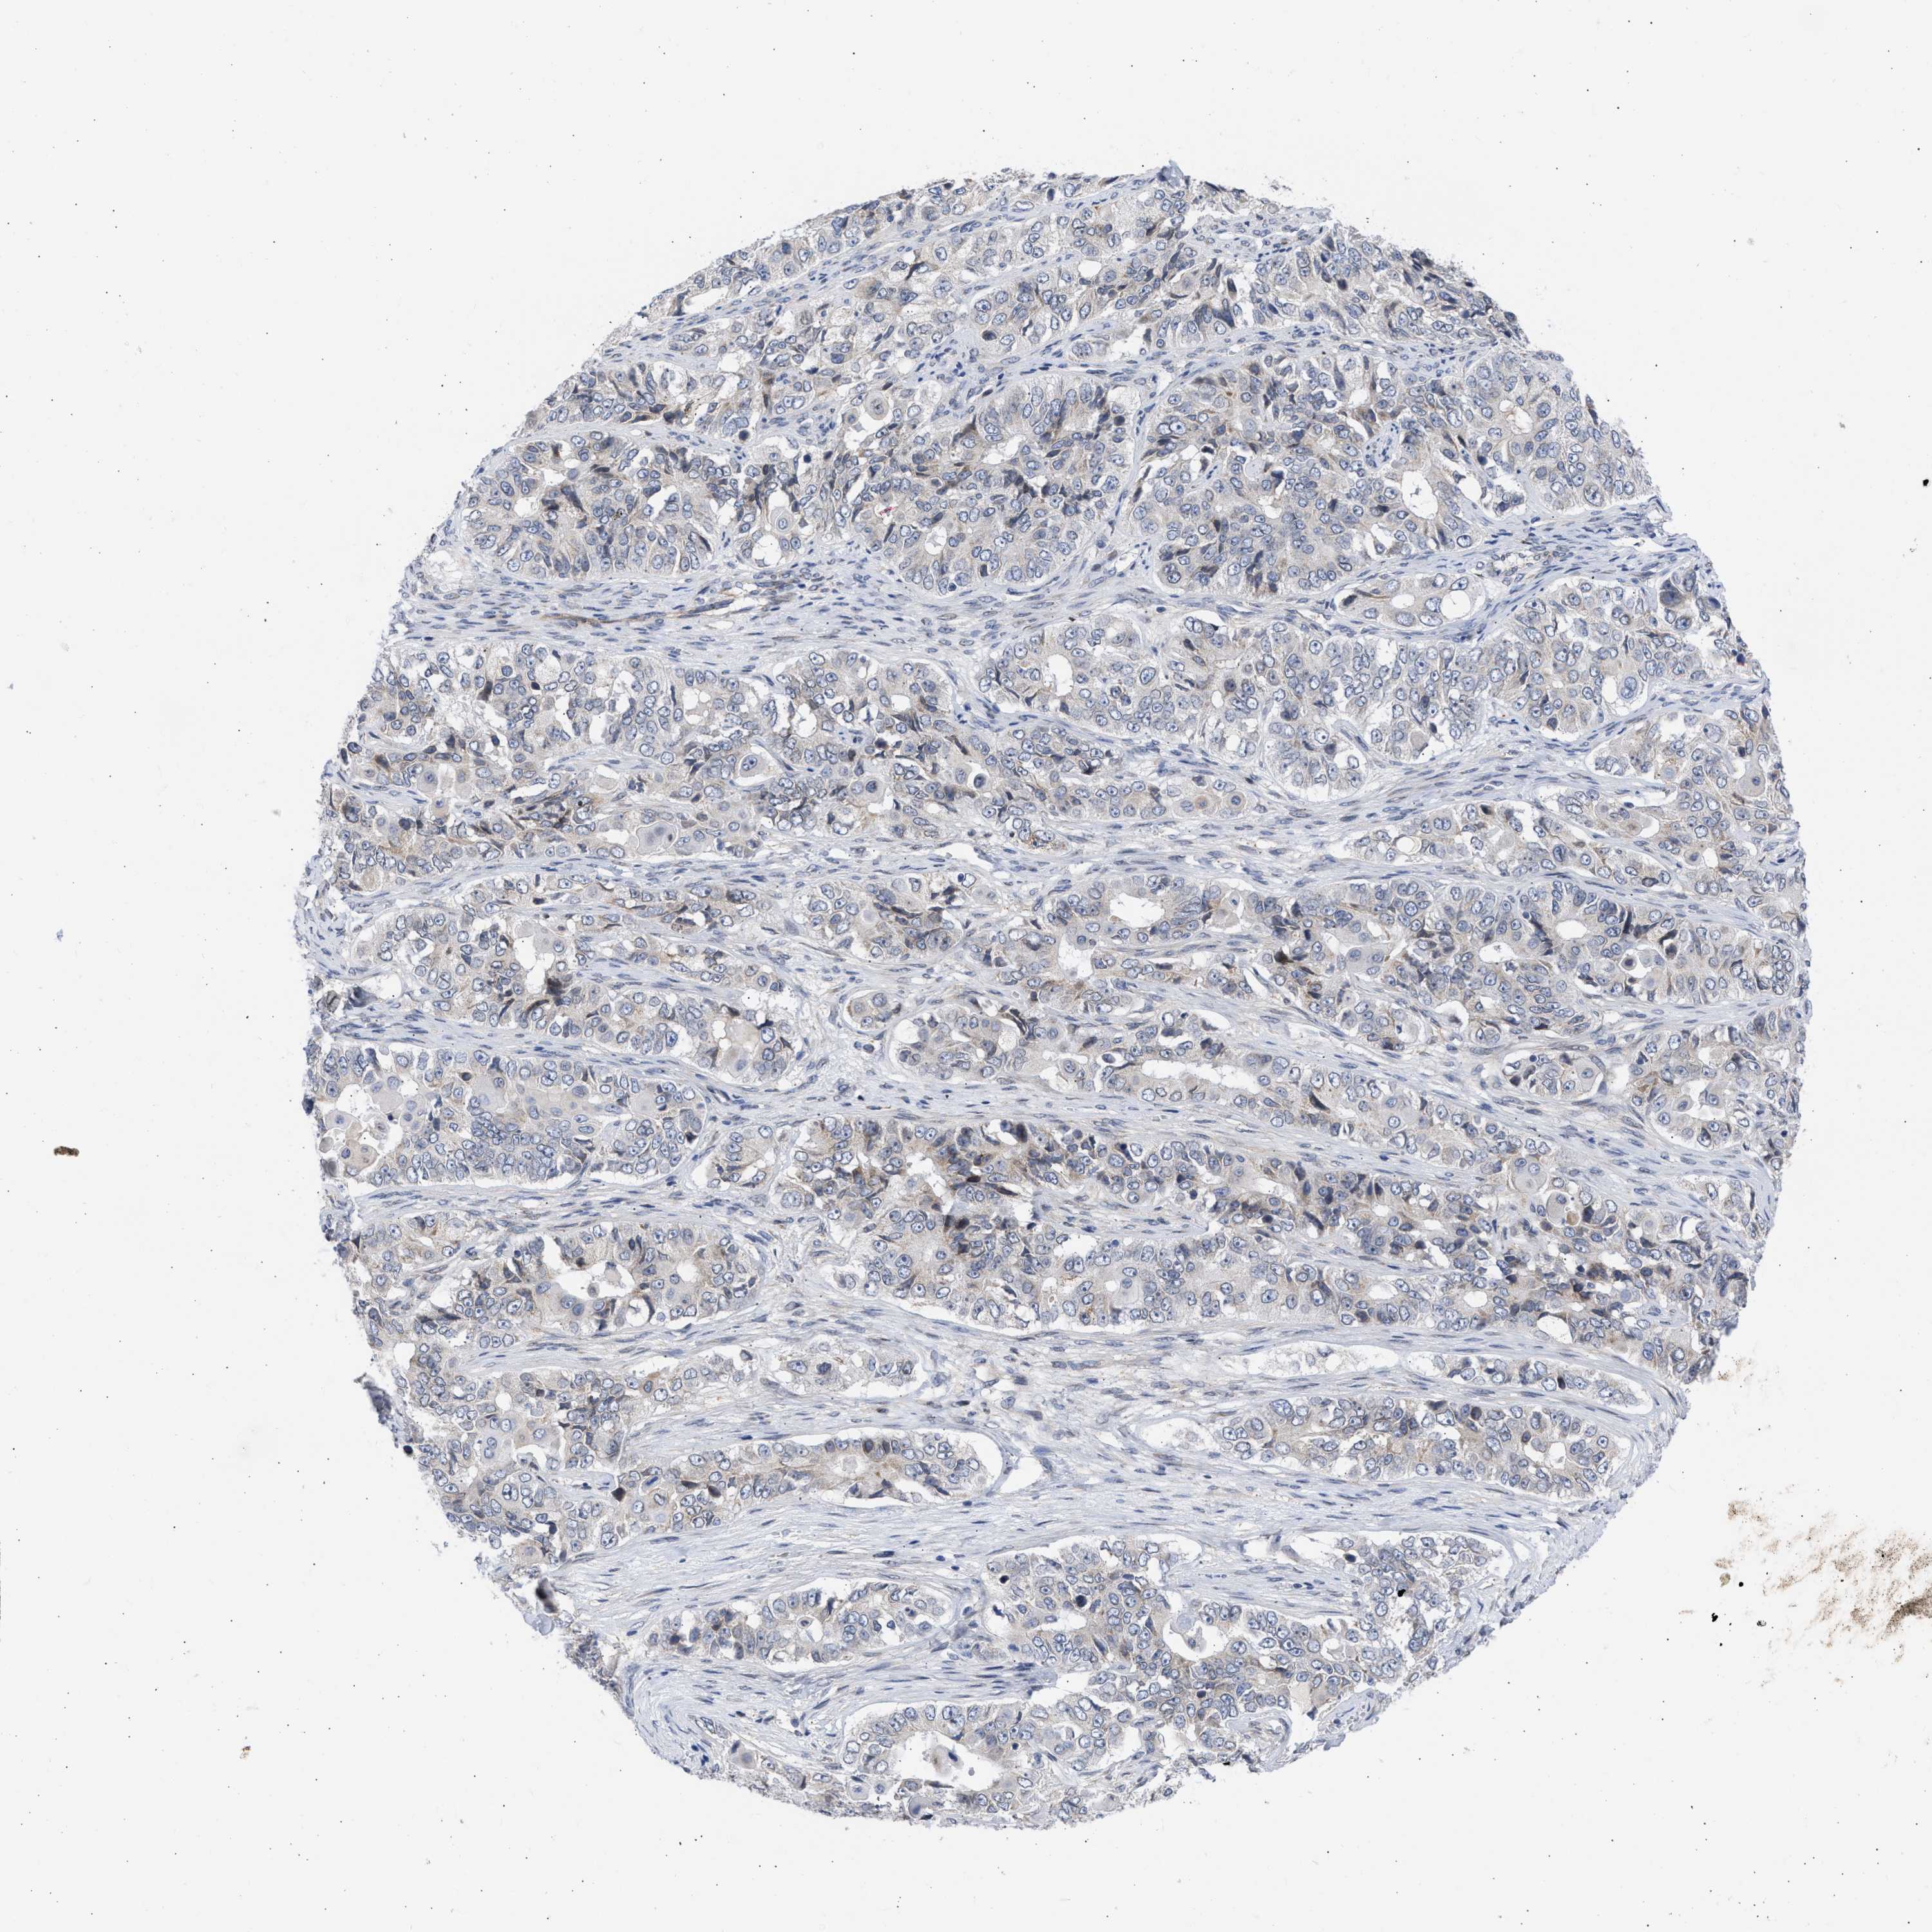

OVARIAN CANCER - Protein expressioni

A mouse-over function shows sample information and annotation data. Click on an image to view it in a full screen mode. Samples can be filtered based on level of antibody staining by selecting one or several of the following categories: high, medium, low and not detected. The assay and annotation is described here.

Note that samples used for immunohistochemistry by the Human Protein Atlas do not correspond to samples in the TCGA dataset.

Antibody stainingi

Antibody staining in the annotated cell types in the current human tissue is reported as not detected, low, medium, or high, based on conventional immunohistochemistry profiling in selected tissues. This score is based on the combination of the staining intensity and fraction of stained cells.

Each image is clickable and will lead to virtual microscopy that enables deeper exploration of all samples and also displays staining intensity scores, fraction scores and subcellular localization as well as patient and tissue information for each sample.

Antibody HPA018401

Cystadenocarcinoma, mucinous, NOS